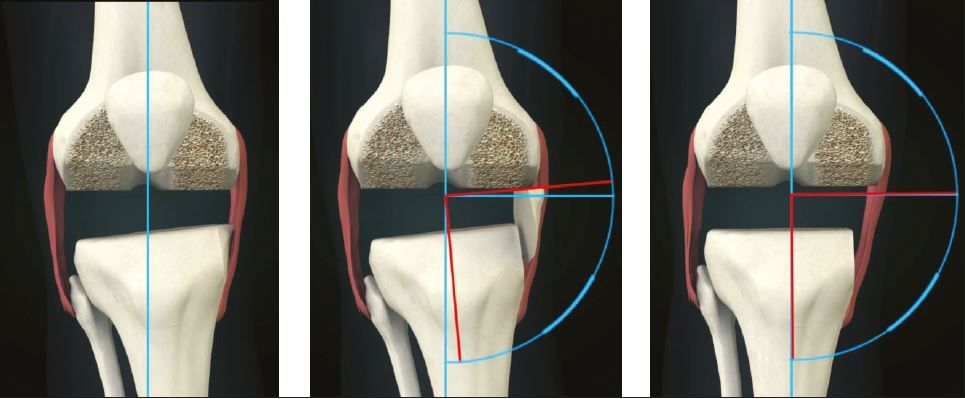

6. The proximal tibial cut affects both flexion and extension gaps equally; the distal femoral cut affects only the extension gap. The posterior femoral cut affects the flexion gap; the anterior femoral cut affects patellar tracking.(Figs 2, 3)